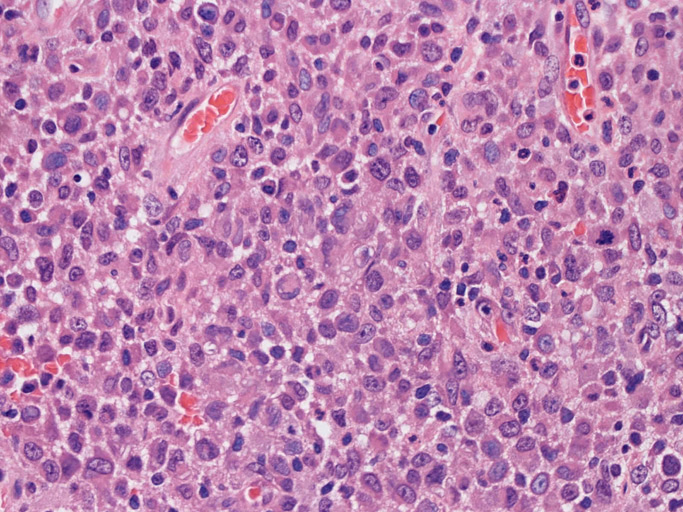

大型細胞の増殖よりなる腫瘍。縦溝,しわ,切れ込みのある核をもった大型細胞も出現する。クロマチンは顆粒状で核小体も明瞭である。核分裂は >50/10hpfと多い。eosinophilsは少ない。壊死が多発することがある。未分化ないし低分化な細胞像, 組織所見のため鑑別診断は多岐にわたり、的確な免疫染色を行う必要がある。

皮膚に異型細胞の浸潤がみられる。異型細胞は表皮内に浸潤するほか、表皮真皮境界部, 真皮, 皮下脂肪組織にもびまん, 結節様の浸潤所見を示す。血管周囲に浸潤、集蔟する所見も多く見られる。 増殖浸潤細胞の核には類円形や腎臓形, またはへこみ, 切れ込み, 溝などを有する多型な核が認められる。クロマチンは粗でvesicularな核が多い。核小体の明らかな核もある。好エオジン性の核内封入体様構造も少数に見られた。mitosisは容易に認められる。hyperchromaticな多型核, bizzarreな細胞が高頻度に認められ異型度は高いと考えられる。細胞質は境界不明瞭, 淡明または泡沫様の 好エオジン性胞体である。